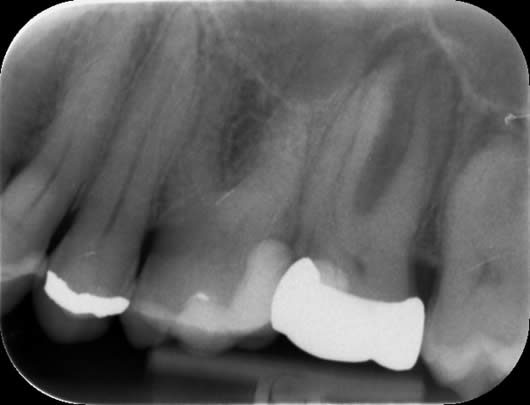

Case 1: Root canal treatment – long roots.

This patient presented with a history of a dull pain and swelling from his upper left second molar (UL7). The tooth had a crown and was tender when tapped. A radiograph (X-ray photograph) showed that there was a large shadow around the roots. This shadow indicates bone loss caused by infection within the root canals. The diagnosis for this tooth was ‘Chronic apical periodontitis’; and the treatment options were either extraction or root canal treatment. After discussion with the patient, we decided to proceed with root canal treatment. As the crown was in good condition, we decided to keep it in place and access through the top of it. This way, a new crown would not be needed after our treatment. In this tooth, all the canals were found; they were long but after careful progress we were able to negotiate to the ends of the roots. This is important as it means we can take our disinfectant solutions to the full length of the canals, enhancing our cleaning potential. The canals were prepared (enlarged to improve penetration of the cleaning solutions), cleaned and filled. A radiograph taken after one year shows good healing as the ‘shadow’ has gone due to regeneration of bone.

Before treatment UL7 - note the ‘shadowing’ around the roots.

Following root canal treatment - the ‘white lines’ are the root fillings within the root canals.

One year review – note the healing of the previous ‘shadow’.